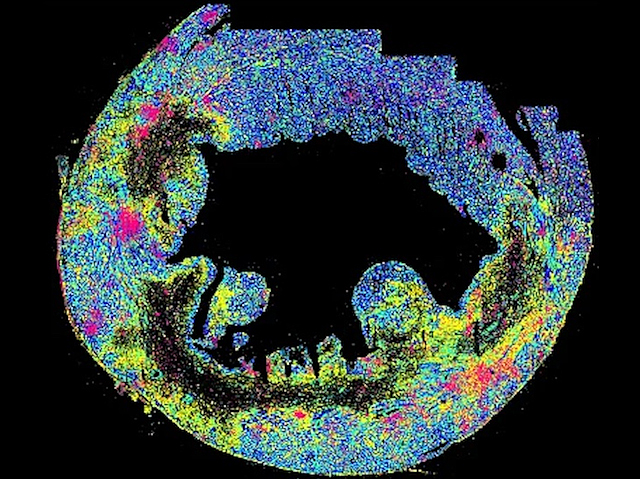

Inflamed Borders

A heart attack or myocardial infarct kills zones of heart muscle provoking inflammation – until now thought to be the work of immune cells – at the injury site. This study uncovers an inflammatory response can also be initiated by cardiomyocytes [heart muscle cells] at the border of the infarct, a risk for further tissue damage and a potential therapeutic target